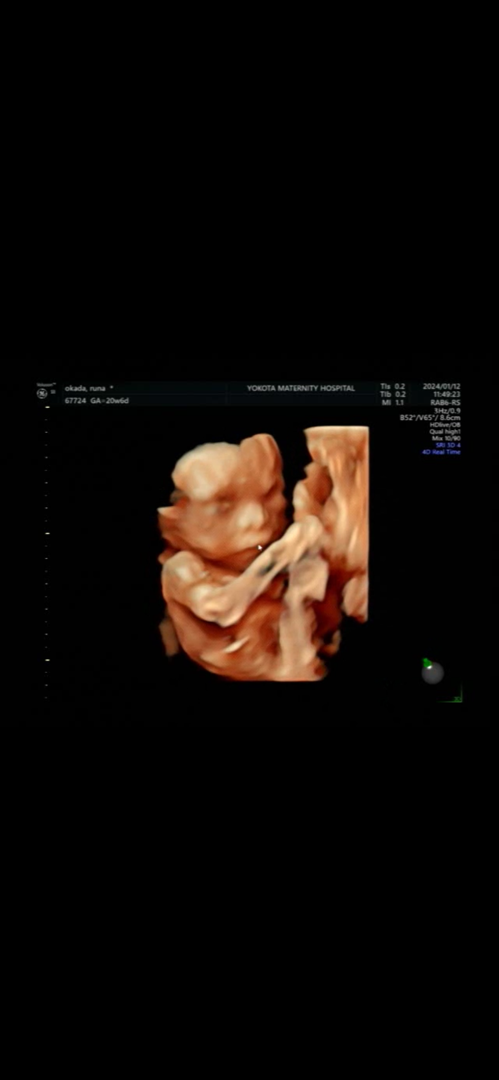

AI顔診断

パパ似?まま似?